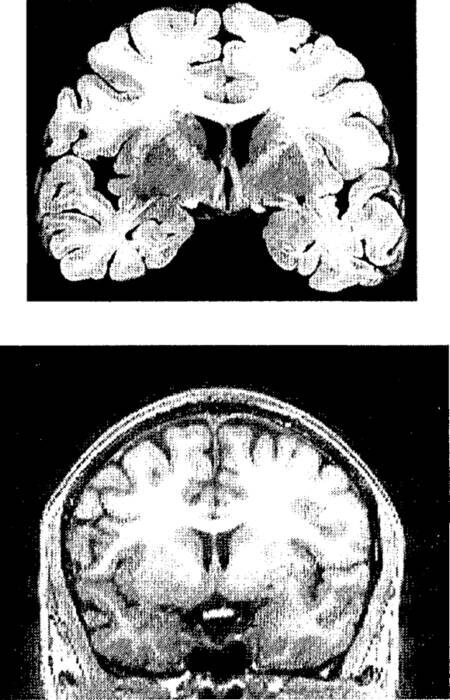

Рис. п.2. Пример полученного с помощью МРТ структурного изображения мозга и срез мозга, извлеченного из трупа.

Вверху фотография одного из срезов мозга, извлеченного из черепа после смерти и нарезанного тонкими слоями. Внизу изображение одного из слоев мозга живого человека, полученное методом магнитно-резонансной томографии (МРТ).

Через несколько лет был разработан другой метод, еще лучше прежнего, магнитно-резонансная томография (МРТ). В МРТ используются не рентгеновские лучи, а радиоволны и очень сильное магнитное поле.15 В отличие от рентгеноскопии эта процедура совершенно не опасна для здоровья. МРТ-сканер намного чувствительнее к различиям плотности, чем АКТ-сканер. На изображениях мозга живого человека, получаемых с его помощью, различимы разные типы тканей. Качества таких изображений не ниже, чем качество фотографий мозга, после смерти извлеченного из черепа, законсервированного химикатами и нарезанного тонкими слоями.